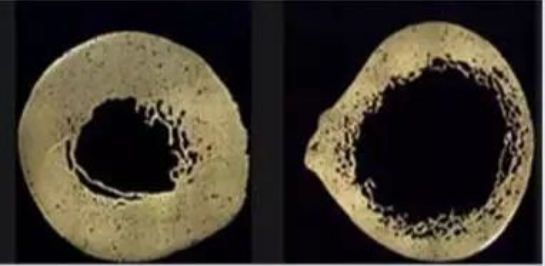

骨质疏松时的骨质流失是先从松质骨开始的

如上图所示,切开长条型的骨头会看见这个情况,左边是正常的皮质骨切面,右边是骨质疏松皮质骨切面。